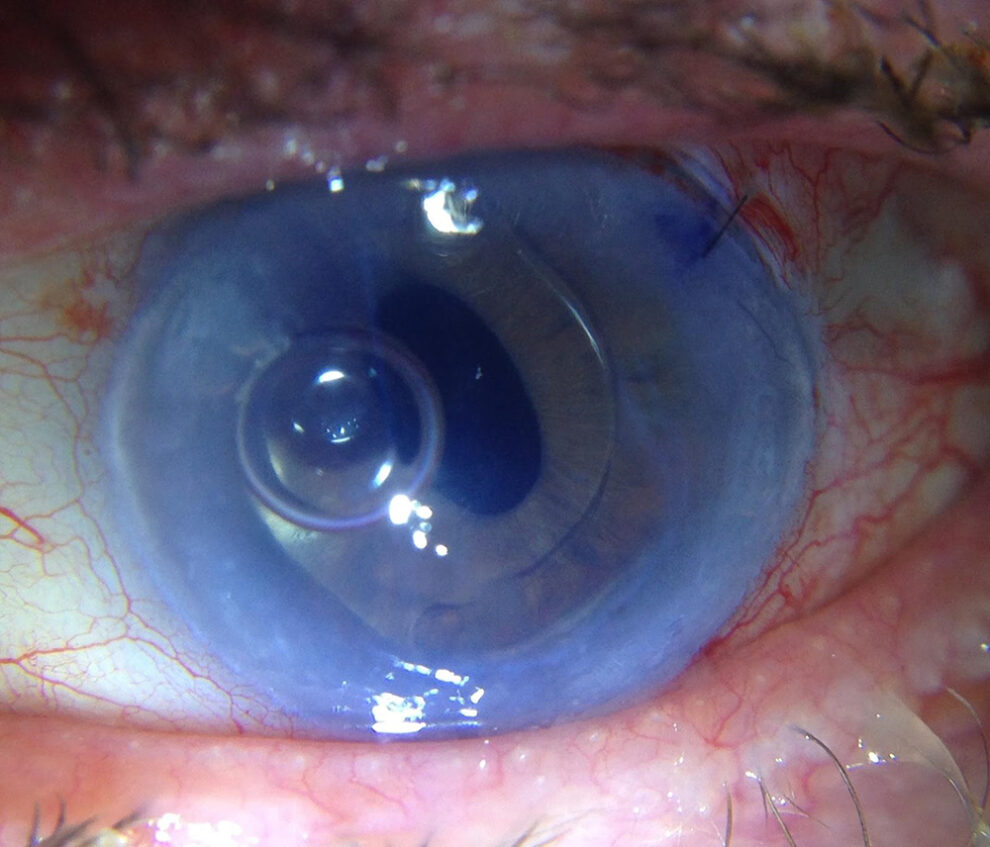

The next images show DSAEK and DMEK transplants. Notice how easy it is to see the DSAEK transplant in the eye, because it has a layer of stroma with it.  DMEK is almost impossible to see unless it is not fully attached yet.  This image of a partially separated DMEK is shown here just so that you can appreciate how thin the graft is when no stroma is transplanted.  You can see how important these grafts are to the cornea, because any area that doesn’t have the graft attached will swell thicker than other areas of the cornea.

This images above were taken with an office examining scope. The image on the left shows the tremendously blurry view of a patient’s cornea before DMEK by Dr. Tenkman.  It was even difficult to appreciate her iris details.  The on the right is 2 weeks after DMEK by Dr. Tenkman.  Her vision was 20/15.  The patient could see much better out of her eye, but notice how much easier it is for us to see in and appreciate her iris details.  At first glance, one would never know that this eye had a DMEK.  A special light technique below allows one to see the DMEK.

This DMEK transplant can only be seen with special lightning techniques.

This image above was taken with an office examining scope. This eye, also, has had DMEK.  At first glance, without special light techniques, it is difficult to appreciate that anything has been done.  The eye appears normal.

Looking without those lighting techniques, this just looks like a normal eye, even under a microscope.